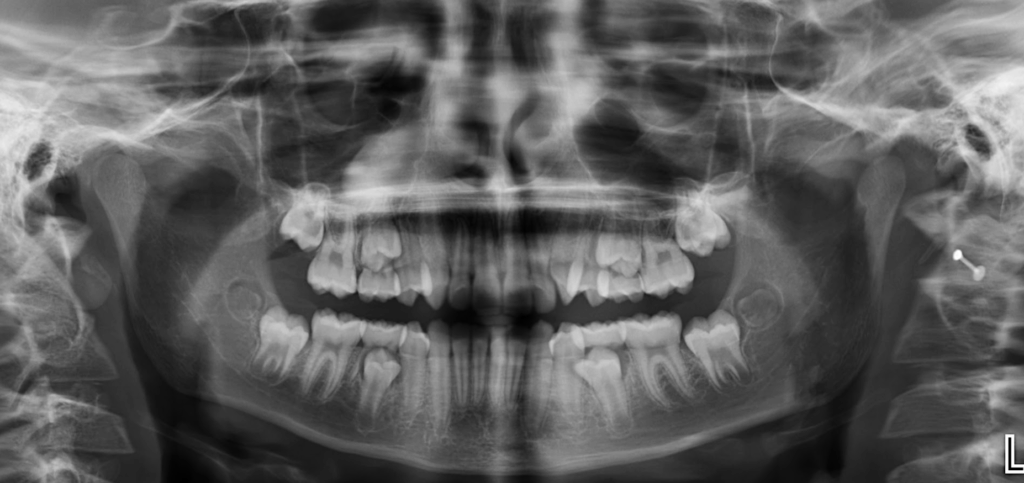

En la radiografía panorámica (Figura 1), se aprecia opacificación de seno maxilar derecho.

Radiografia Panorámica